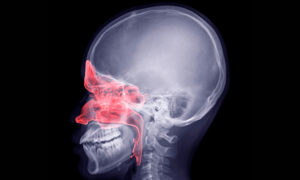

Una manera en que el COVID-19 afecta el corazón es invadiéndolo a través del músculo liso, causando su inflamación, y en casos graves, ocasionando daño permanente — ya sea por cicatrización del músculo cardíaco o por necrosis del tejido. Sin embargo, esto ha sido un tema muy polémico.

Mientras que los datos de imagenología suponen que la inflamación está sucediendo, existen algunos casos documentados en donde la biopsia cardiaca o autopsia muestran claramente la presencia del virus asociada a una miocarditis. Esto puede ser en parte por la indecisión a realizar biopsias en las personas que son aún contagiosas.

La inflamación también puede acumularse en el corazón como resultado de una respuesta exagerada del sistema inmune ante la infección, que produce en el cuerpo la llamada “tormenta de citoquinas”, y aunque es menos directo, este mecanismo de daño es muy común.

Sin importar si es causa directa o indirecta de la infección del coronavirus, la inflamación por sí misma dentro de músculo cardiaco, llamada miocarditis, es una causa muy común de falla del corazón.